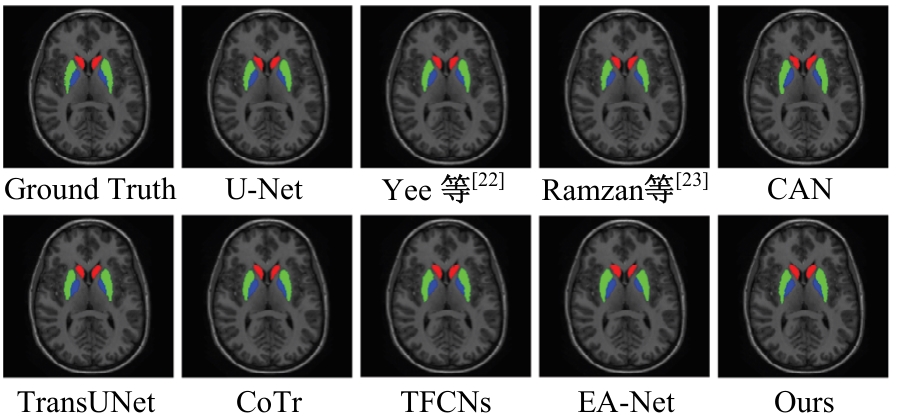

针对脑皮层下组织部分结构(如纹状体)在医学影像中目标小、对比度低,图像分割难度大,在自动医学诊断中应用比较困难的问题,本文基于深度学习的方法提出了一种医学图像分割网络,在磁共振成像中分割组成纹状体的苍白球、尾状核、壳核3部分。本文提出的网络模型具有捕获全局和局部特征的能力,并建立了全局与局部信息的相关性,在深度不退化的同时有效融合不同尺度的深层语义特征和浅层细节特征,实现对纹状体的精确分割。模型在公开的脑部数据集上进行了验证,并与其他先进的方法进行对比,结果表明本文的戴斯相似系数、平均交并比、95%豪斯多夫距离分别为94.26%、90.94%、3.82,均优于其他几种方法,达到了先进水平,这表明本文模型可以提高对纹状体的分割精度,为相关疾病的研究提供依据。

| [22] | Yee E, Ma D, Popuri K, et al. 3D hemisphere-based convolutional neural network for whole-brain MRI segmentation[J]. Computerized Medical Imaging and Graphics, 2022, 95: No.102000. |

| [23] | Ramzan F, Khan M U G, Iqbal S, et al. Volumetric segmentation of brain regions from MRI scans using 3D convolutional neural networks[J]. IEEE Access, 2020, 8: 103697-103709. |

| [26] | Li Z, Zhang C, Zhang Y, et al. CAN: context-assisted full attention network for brain tissue segmentation[J]. Medical Image Analysis, 2023, 85: No.102710. |

| [27] | Xie Y, Zhang J, Shen C, et al. Cotr: efficiently bridging cnn and transformer for 3d medical image segmentation[C]∥The 24th International Conference on Medical Image Computing and Computer Assisted Intervention, Strasbourg, France,2021: 171-180. |

| [28] | Chen J, Lu Y, Yu Q, et al. Transunet: Transformers make strong encoders for medical image segmentation[J/OL].[2023-10-25]. . |

| [29] | Li Z, Li D, Xu C, et al. TFCNs: a CNN-transformer hybrid network for medical image segmentation[C]∥International Conference on Artificial Neural Networks,Bristol, UK, 2022: 781-792. |

| [30] | Wang K, Zhang X, Zhang X, et al. EANet: iterative edge attention network for medical image segmentation[J]. Pattern Recognition, 2022, 127: No.108636. |